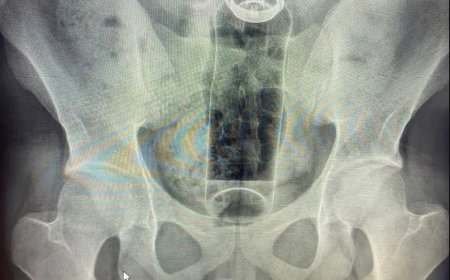

No hospital, Beatriz passou por um procedimento cirúrgico e permaneceu internada na Unidade de Terapia Intensiva (UTI), sob cuidados intensivos. Após quatro dias de internação, a adolescente não resistiu às complicações clínicas e morreu.